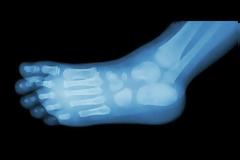

Άκανθα φτέρνας: Αιτίες και αντιμετώπιση

Η άκανθα φτέρνας είναι ένα ασβεστοποιημένο σημείο στο οστό της φτέρνας. Πρόκειται για ένα πρόβλημα που μπορεί να προκαλέσει μεγάλο πόνο και δυσκολία όταν προσπαθείτε να κινήσετε